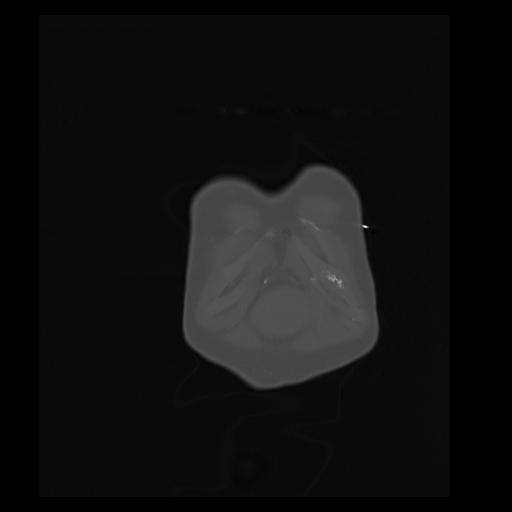

32 PULMON,CE,Coronal,3.000,PULMON,Coronal,